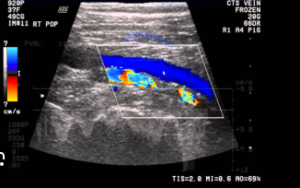

A Venous Doppler (also known as Venous Color Doppler Ultrasound) is a non-invasive imaging test that uses sound waves to evaluate blood flow in the veins, mainly in the legs, arms, or neck.

It shows both the structure of the veins and how efficiently blood flows through them — helping your doctor plan the right treatment.

With the help of a Venous Doppler, doctors can visualize real-time blood movement, detect clots or reflux, and plan effective treatment to restore healthy circulation.

Advanced Color & Spectral Doppler Technology

Blood flow direction and velocity